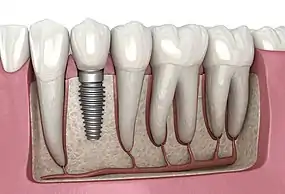

A dental implant (also known as an endosseous implant or fixture) is a prosthesis that interfaces with the bone of the jaw or skull to support a dental prosthesis such as a crown, bridge, denture, or facial prosthesis or to act as an orthodontic anchor. The basis for modern dental implants is a biological process called osseointegration, in which materials such as titanium or zirconia form an intimate bond to the bone. The implant fixture is first placed so that it is likely to osseointegrate, then a dental prosthetic is added. A variable amount of healing time is required for osseointegration before either the dental prosthetic (a tooth, bridge, or denture) is attached to the implant or an abutment is placed which will hold a dental prosthetic/crown.

A typical conventional implant consists of a titanium screw (resembling a tooth root) with a roughened or smooth surface. The majority of dental implants are made of commercially pure titanium, which is available in four grades depending upon the amount of carbon, nitrogen, oxygen and iron contained.[21] Cold work hardened CP4 (maximum impurity limits of N .05 percent, C .10 percent, H .015 percent, Fe .50 percent, and O .40 percent) is the most commonly used titanium for implants. Grade 5 titanium, Titanium 6AL-4V (signifying the titanium alloy containing 6 percent aluminium and 4 percent vanadium alloy) is slightly harder than CP4 and used in the industry mostly for abutment screws and abutments.[22]: 284–285 Most modern dental implants also have a textured surface (through etching, anodic oxidation or various-media blasting) to increase the surface area and osseointegration potential of the implant.[23]: 55 If C.P. titanium or a titanium alloy has more than 85% titanium content, it will form a titanium-biocompatible titanium oxide surface layer or veneer that encloses the other metals, preventing them from contacting the bone.[24]